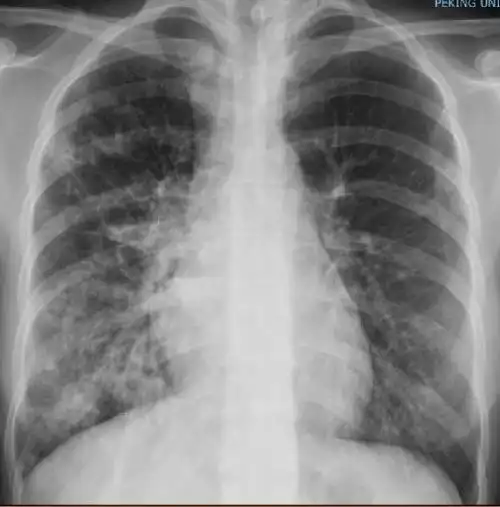

一位36岁细菌性肺炎女性患者的肺部x光影像:双肺已出现斑片状状阴影

记录孩子2年半以来第一次重症肺炎